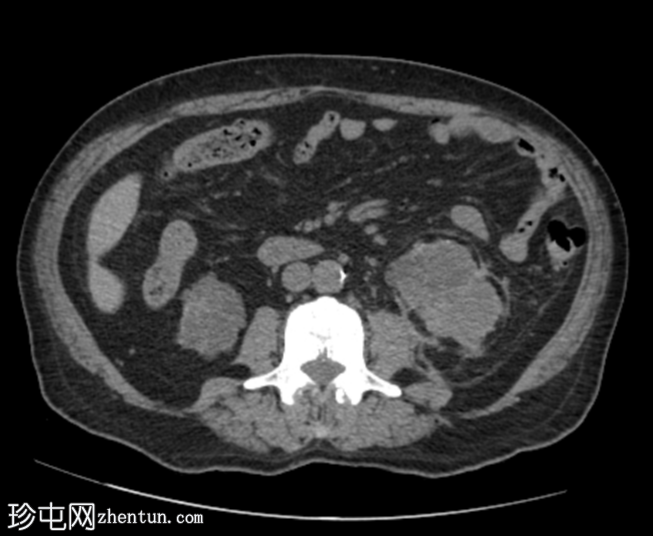

CT扫描

轴位

平扫

再次显示双侧肾囊性疾病,可见多个复杂(出血性)囊肿,以及与左肾上极复杂出血性囊肿相连的左肾周血肿。左肾周脂肪间隙模糊。

双侧多发性小肾结石。

弥漫性骨硬化,提示肾性骨营养不良。